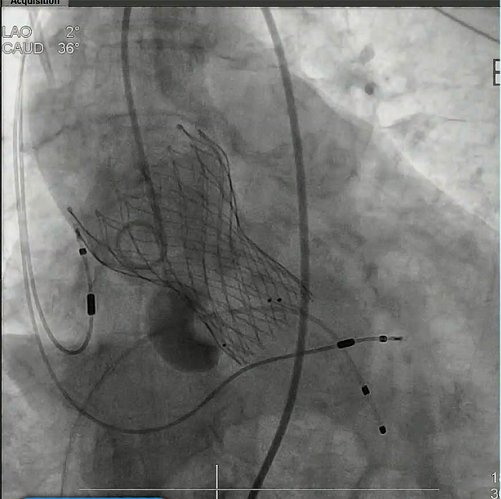

瓣膜在瓣环下精准定位,稳定释放

瓣膜释放后结果

最后造影

最后造影亦未见反流,患者情况良好,手术顺利完成。